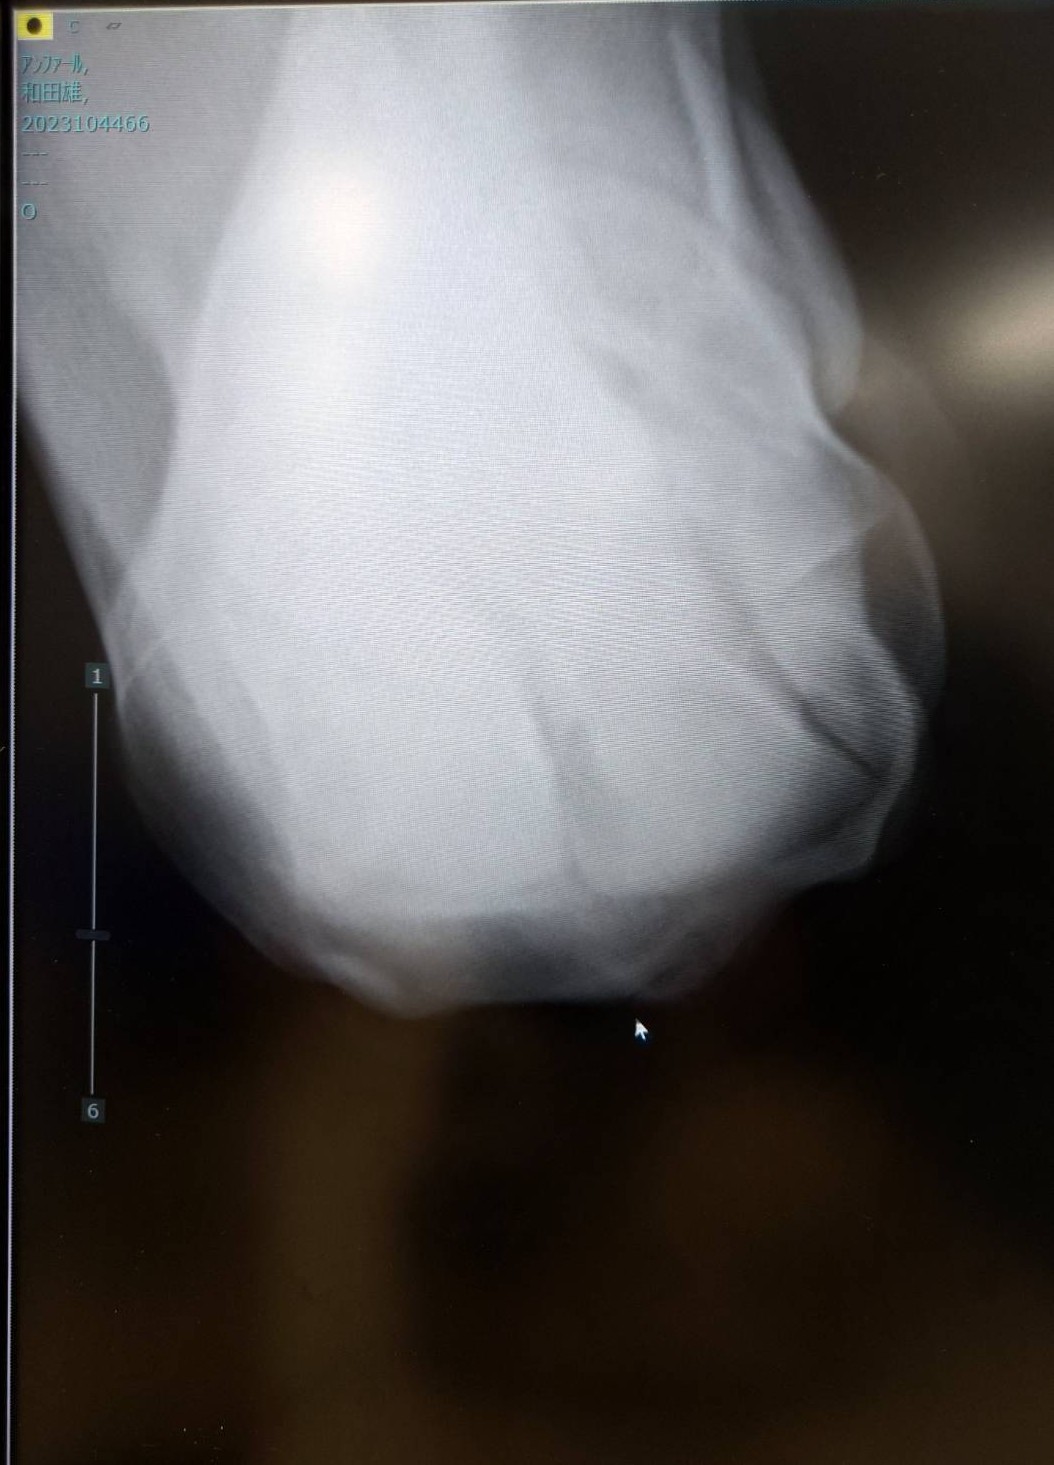

※2026年2月10日京都2R出走後、左膝が腫れたことからレントゲン撮影を行ったところ、左前橈骨遠位端剥離骨折が判明。事故見舞金9号(競走中の事故により事故発生の日から6カ月以上出走できなくなった場合)の適用を受けています。